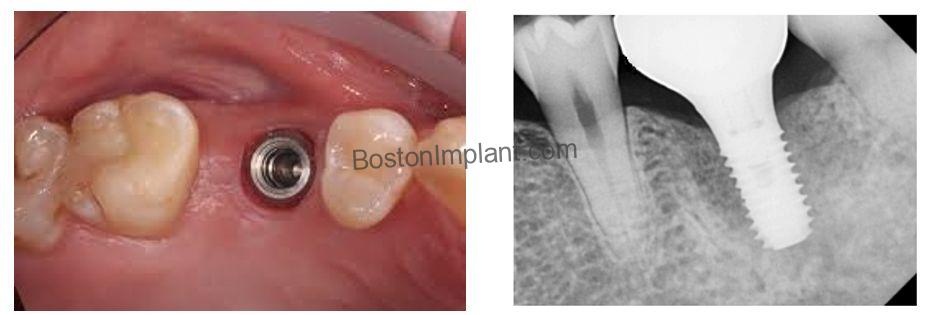

Finally, the connection design presents another key difference. The connection of bone-level implants is situated below the gum line, making visual confirmation of a precise abutment-implant fit challenging. This can sometimes lead to unnoticed misfits. (As illustrated in the green circle in the image below, a gap can exist between the abutment and the implant.)

Conversely, the platform of tissue-level implants is located at the gum level, facilitating a clinically easier and more accurate assessment of the abutment fit.

- Precise Initial Placement: While the integrated gingival component of tissue-level implants offers advantages, accurate placement is critical. The gingival margin must be precisely centered at the ideal position. At Boston Finesse Implant Center, we utilize surgical guides to ensure the accurate placement of every dental implant.